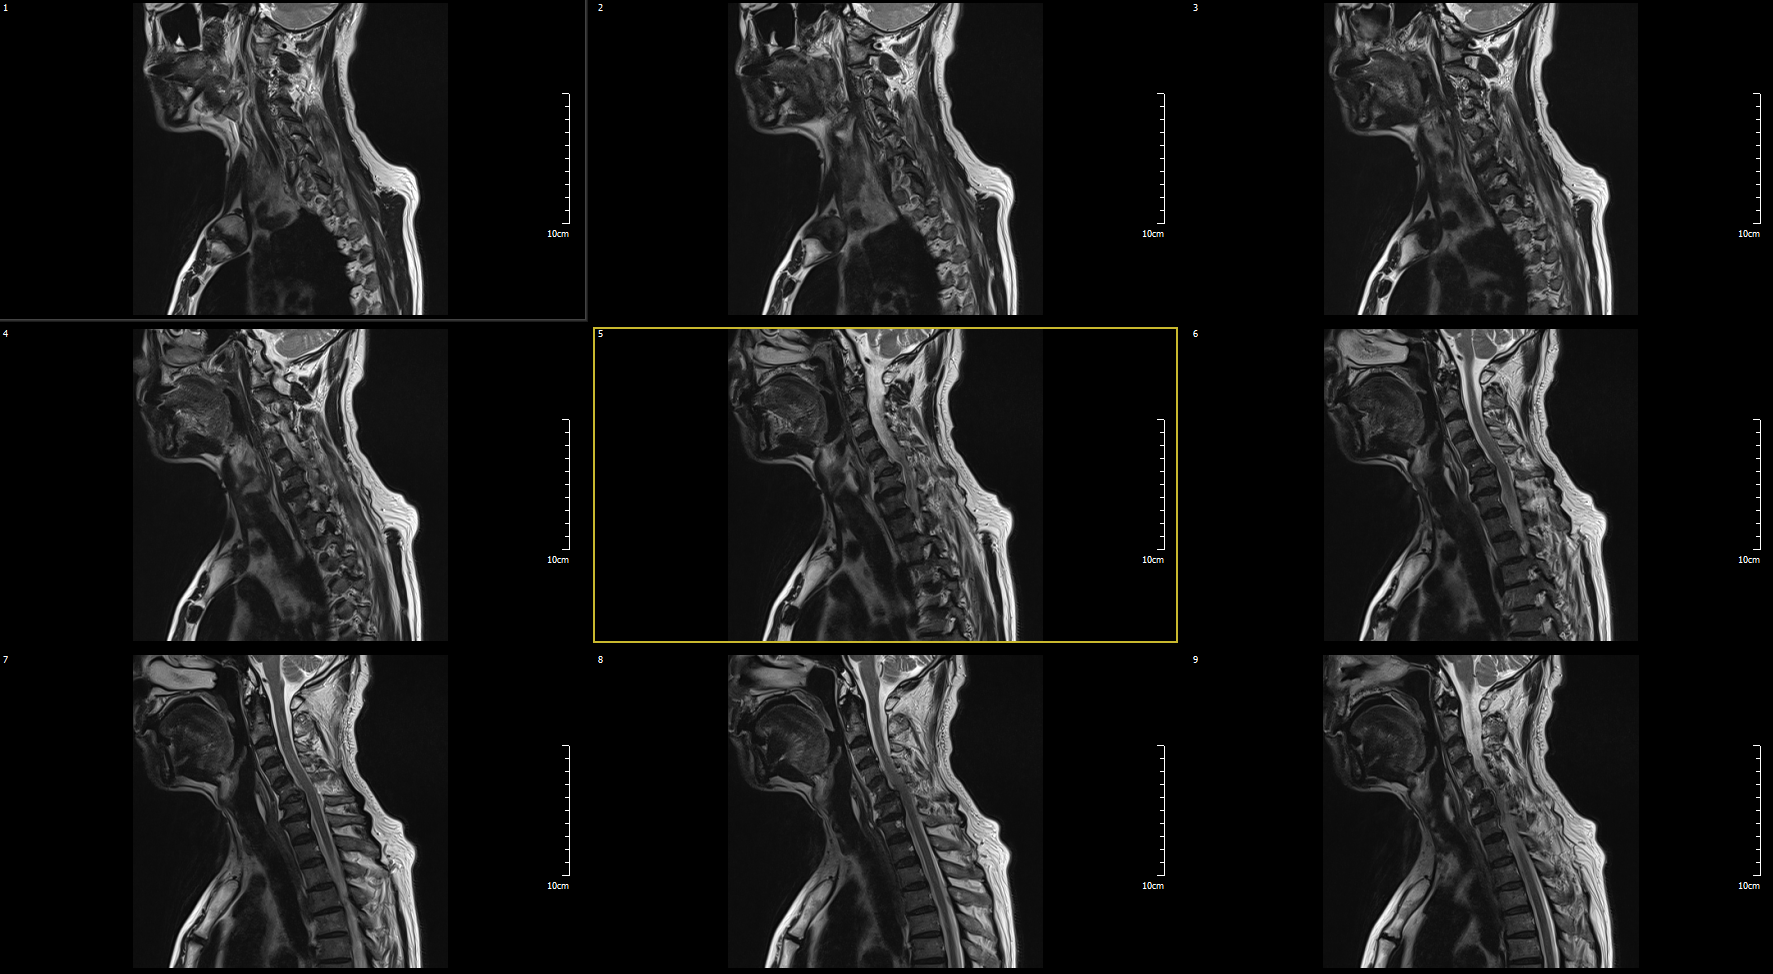

MRI

C5-6 : Ruptured HCD, Rt